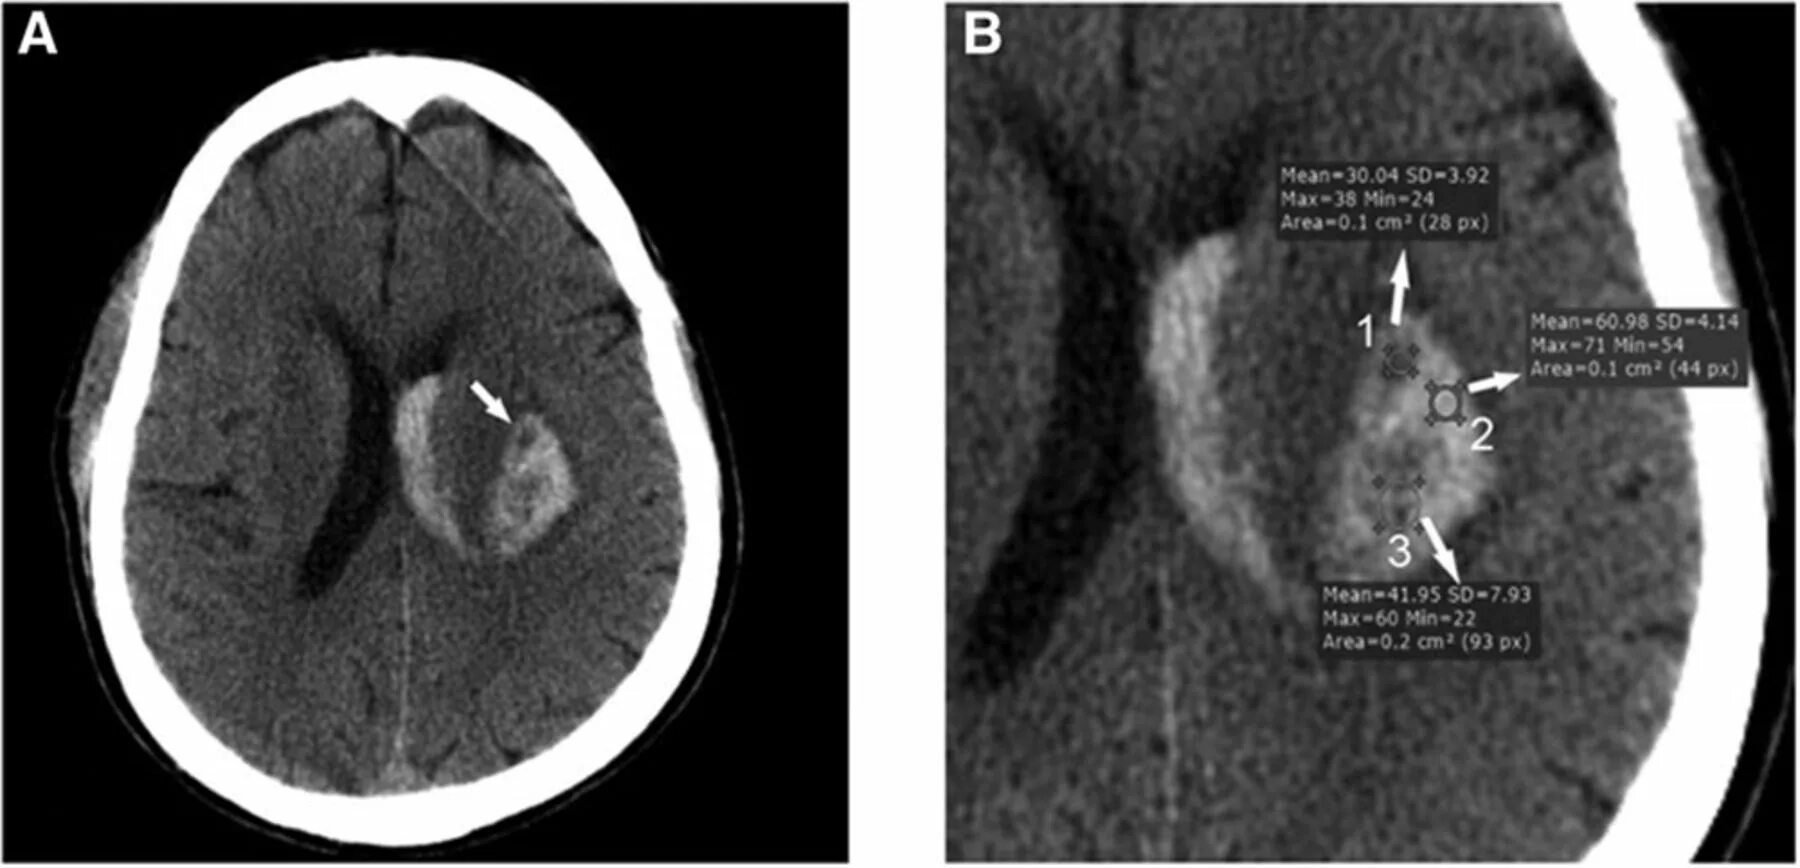

Плотность на кт